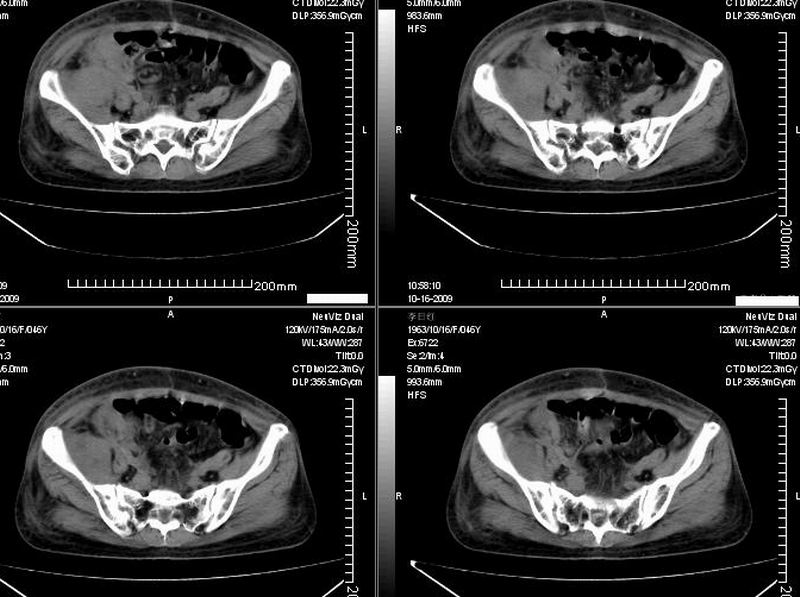

女:46y:一年前宫颈癌术后,现右下腹抚及肿块。

考虑宫颈癌术后复发周边侵犯/右中下腹及双侧腹股沟淋巴结转移。